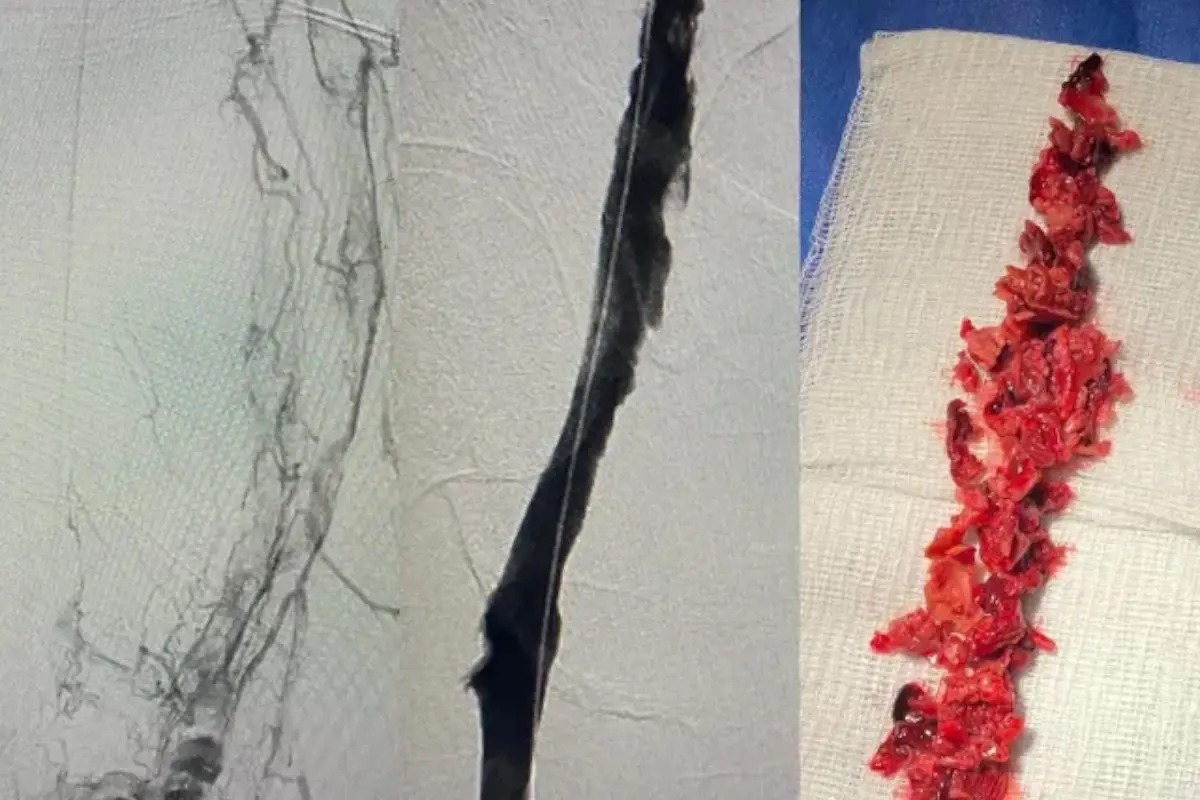

Blood clot removal

Your provider may perform a catheter-assisted blood clot removal. After making a very small incision, they insert a flexible tube (catheter) into a blood vessel and guide the catheter to the clot. Then, they use a tool to break up the clot or release a thrombolytic medicine.